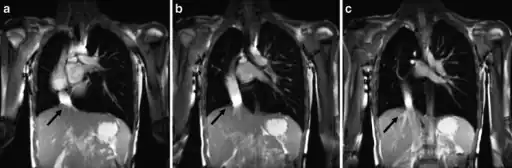

a-c) Scimitar syndrome in a young male- Breath-hold coronal 2-D steady-state free precession demonstrates the anomalous partial pulmonary venous return

The diagnosis is made by transthoracic or transesophageal echocardiography and selective pulmonary angiography.[6] More recently by CT angiography or MR Angiography.

Pulmonary angiography demonstrates anomalous arterial supply to right lower lobe.[6]